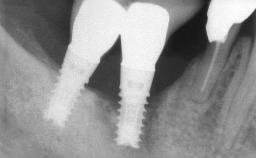

Oral implants are highly successful and offer long-term benefits, especially in the rehabilitation of edentulous patients or patients with oral defects following ablative tumor surgery (Albrektsson and coworkers 1986), and also after radiation therapy (Schiegnitz and coworkers 2014). With the number of implants placed globally going into the millions, implant dentists have observed some rare adverse events. Although carcinogenesis around implants is an exceedingly rare phenomenon, we recently reported about 15 patients treated for carcinomas adjacent to implants at our clinical department over a period of fifteen years (Moergel and coworkers 2014). The following case represents a patient of this cohort; it discusses possible risk factors and makes suggestions for a recall schedule. A 70-year-old woman was referred to our outpatient department for evaluation of a rapidly growing macroscopic alteration of the mucosa in the left mandible.

# of Implants 4